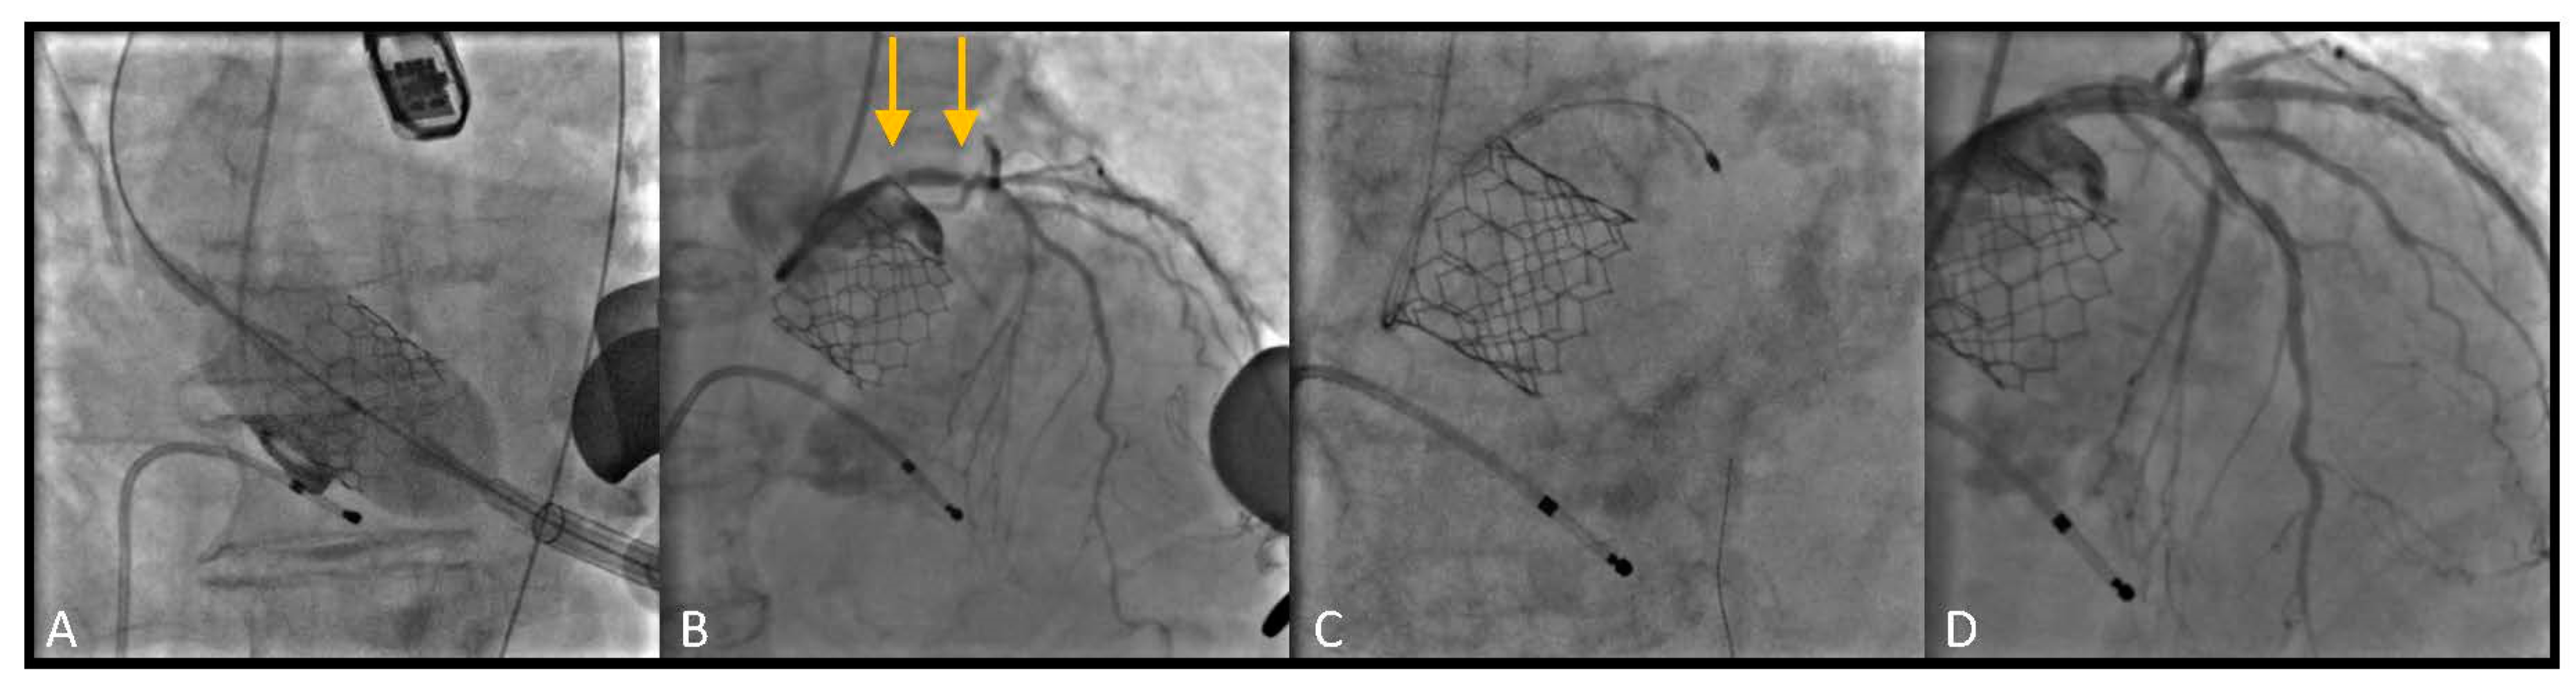

In addition, in several patients, other than the angiographic evaluation of the coronary calcification, the coronary analysis of the pre-TAVI CT scan has added important information regarding the extension of the vessel calcification (see as an example in Figure 1, part A).

Most patients underwent TAVI via trans-femoral route (Figure 1). In 5 cases (26.3%) TAVI procedure was performed through a trans-apical access due to important vascular disease involving the ilio-femoral axis, not suitable for the trans-femoral TAVI delivery systems (Figure 2).

Figure 1. Rotational atherectomy (RA) following Medtronic CoreValve deployment by Trans-Femoral approach. (A) Pre-TAVI CT views showing severe calcification of LAD; (B) Pre RA angiographic evaluation of the lesion: proximal LAD presented severe calcified lesion (arrow); (C) Multiple burr (RotaPro 1.25 mm) advancements; (D) Final result, after stent deployment and post dilation.